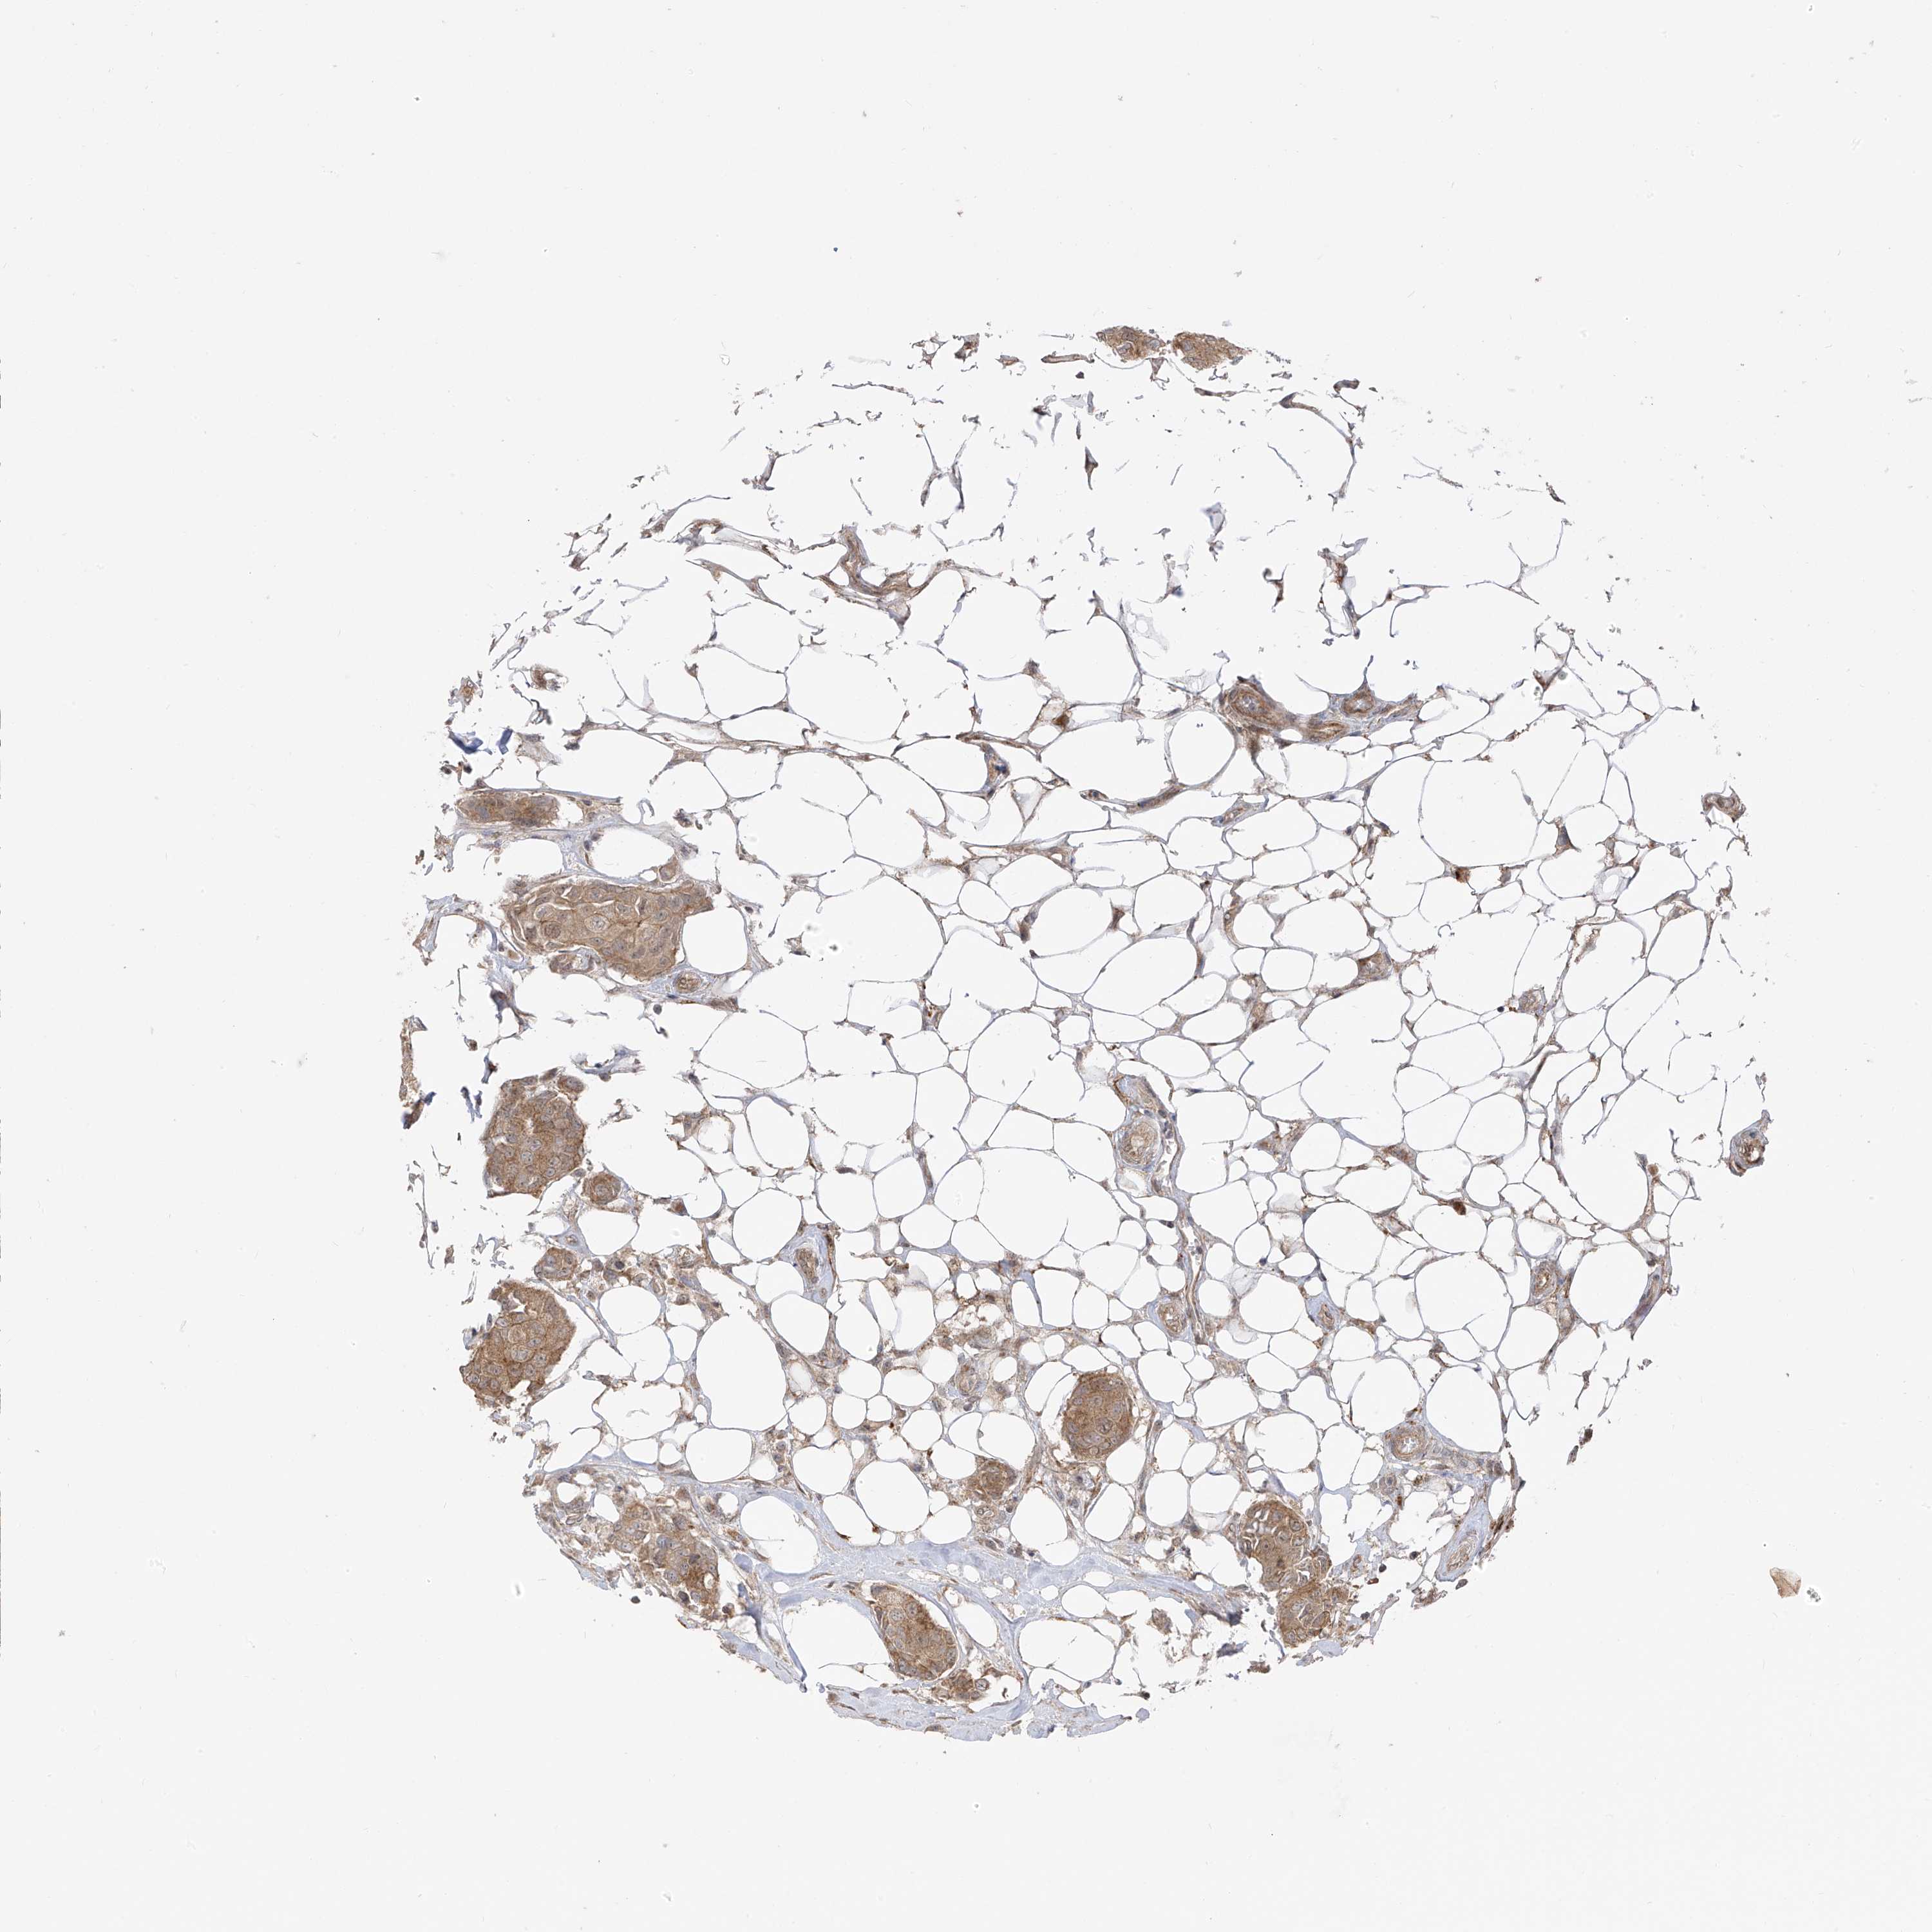

CANCER BREAST CANCER Show tissue menu

BRCA TCGA BRCA VALIDATION PROTEIN EXPRESSION

ANTIBODIES

AND

VALIDATION